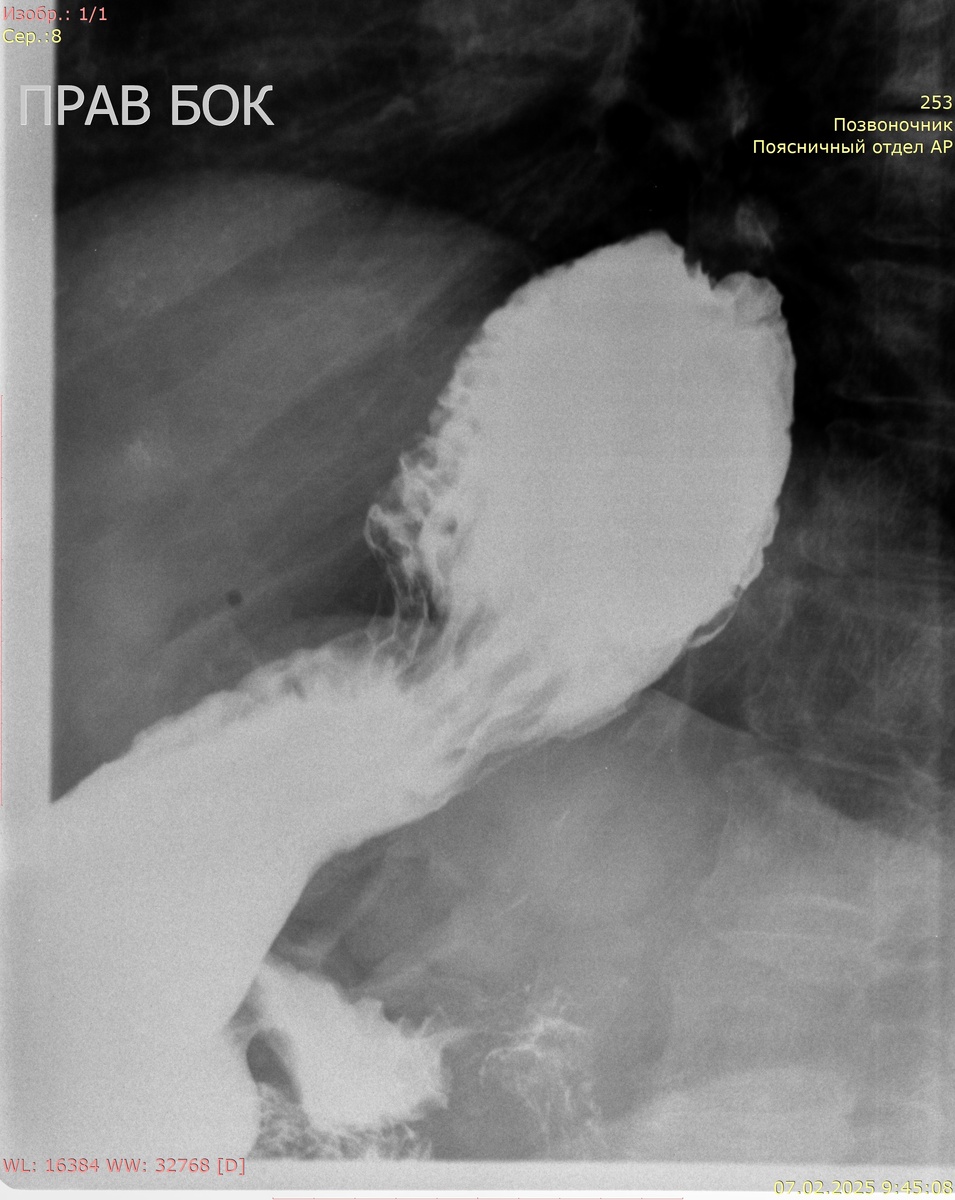

Рентгенография желудка с сульфатом Ва:

Кардиальный жом функционирует. Желудок деформирован, объем обычный, до 1/2 объема в проекции грудной полости. Контуры желудка ровные, отвесные, участков деформации не выявлено. Рельеф слизистой не изменен, складки не утолщены. Контраст своевременно поступает в ДПК. В положении стоя определяется пролабирование кардиальных складок выше диафрагмы размерами 80 мм х 63 мм (лежа до 118 мм х 88 мм).

Заключение: фиксированная грыжа пищеводного отверстия диафрагмы 4 ст.

Желудок стоя